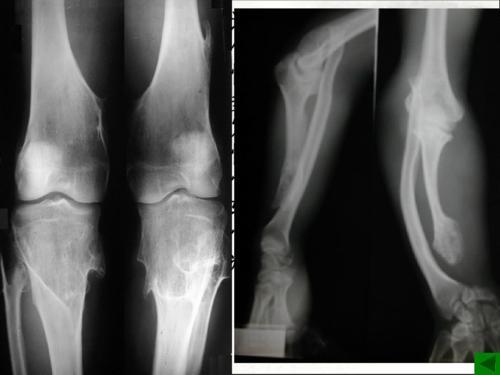

儿童骨肉瘤图片

儿童骨肉瘤图片,儿童骨肉瘤好发部位

儿童骨肉瘤好发部位

骨肉瘤图片

骨肉瘤x线

骨肉瘤影像学